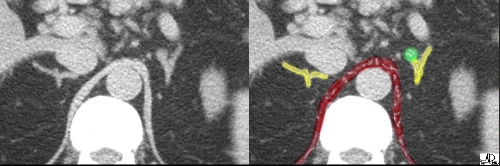

![]() The crura of the diaphragm (maroon overlay) can be seen as muscle bundles alongside the vertebral body and surrounding the aorta. The limbs of the adrenal gland (yellow overlay)should not be thicker than the crura. In this instance, the right adrenal gland is normal. The knobbly appearance of the left gland is also normal. At first glance it does appear thickened and concerning, but when the bend of the medial limb is recognized as a structural consequence of compression, the appearance becomes less concerning. The distinction between “knobbly normal” and “knobbly hyperplasia” is sometimes difficult.Courtesy of: Ashley Davidoff, M.D. adrenals-00023 |

![]() The right adrenal gland, in this case, looks exactly like the inserted drawing of the “wishbone”. This represents the typical appearance of the glands – the right long and thin, and the left short and stout. The bright red overlays represent some of the branches of the adrenal arteries. Courtesy of: Ashley Davidoff, M.D. adrenals-00030 |

| This coronal T1-weighted image has been overlayed with the arterial anatomy of the adrenal. Each gland receives arterial blood from three arteries – the superior, middle and inferior adrenal arteries.

In this early phase arterial CT, multiple branches of the adrenal arteries are overlayed in red. Branches of the inferior phrenic arteries are seen in close association with the crura of the diaphragm. The veins have not yet filled with contrast.Courtesy of: Ashley Davidoff, M.D. |